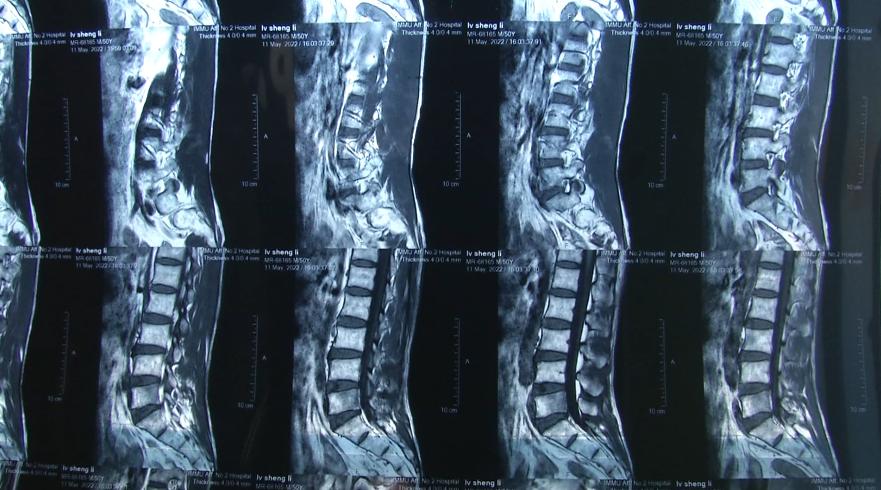

呂師傅摔傷后,在幾位工友的陪同下到醫(yī)院做了檢查,當(dāng)時(shí)并沒(méi)有查出異樣,于是他就回了家。幾天后呂師傅覺(jué)得疼痛加重,再次到醫(yī)院做檢查,發(fā)現(xiàn)腰椎的上部骨折了。

呂師傅:人家主任說(shuō)就得臥床休息,不叫站起來(lái)行走,臥床休息一個(gè)半月到兩個(gè)月,半年以后才能徹底好了。